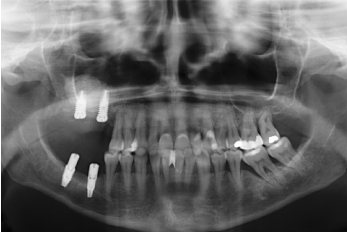

Presentamos el caso de una paciente femenina de 58 años que acude a la consulta dental para valoración de los molares 16 y 17 por dolor y movilidad. En la exploración clínica se observa movilidad de ambos y supuración a nivel del surco. La radiografía confirma nuestro diagnóstico encontrándonos con una pérdida ósea considerable y una perforación sinusal a nivel del ápice de ambos molares (Figura 2).

Se realiza la extracción de ambos y la regeneración de los alveolos con PRGF-Endoret para lograr el sellado de la perforación y una evolución lo más favorable posible para la posterior inserción de los implantes en la zona. Tras dos meses podemos observar en el Cone-Beam dental que la perforación se ha cerrado completamente pero el volumen óseo residual en altura para la inserción de los implantes es insuficiente, existiendo únicamente un 2 mm de altura ósea (Figuras 3 y 4).